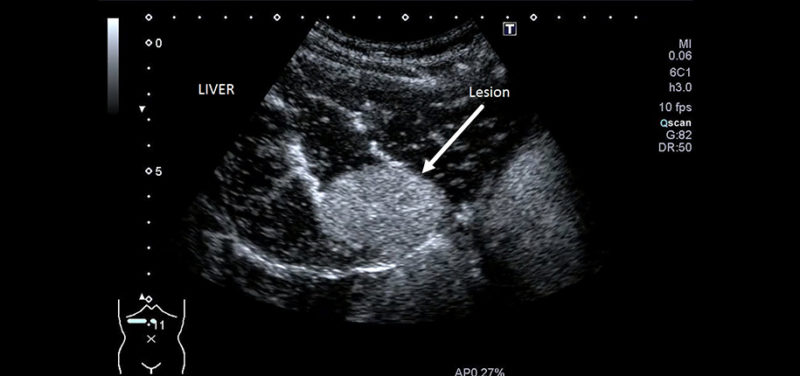

Image: This image shows a lesion within the liver, enhanced with ultrasound contrast. A lot of critical information regarding the lesion’s potential for malignancy can be garnered by observing the pattern and time of contrast “wash in” as well as the “wash out.”

Image: This image shows a lesion within the liver, enhanced with ultrasound contrast. A lot of critical information regarding the lesion’s potential for malignancy can be garnered by observing the pattern and time of contrast “wash in” as well as the “wash out.”

The time it takes for the contrast to “wash in” or “wash out” of a lesion, as well as the pattern of wash in/out, provides critical information to differentiate benign from malignant tissue. The sensitivity and specificity of contrast-enhanced ultrasound in differentiating suspicious lesions and tissues is outstanding, rivaling that of contrast enhanced CT or MR exams.